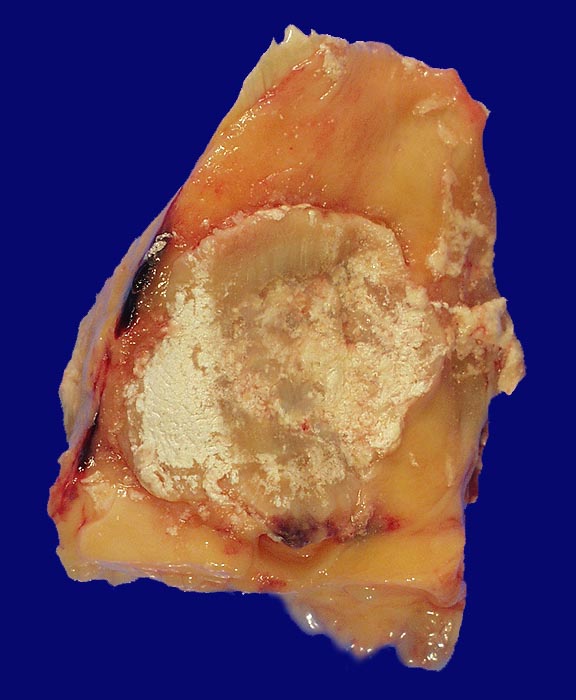

Bei einer Gicht sind kristallin ausgefällte Natriumuratkristalle in den neutrophilen Granulozyten des Gelenkergusses und kalkweisse Auflagerungen am Gelenkknorpel nachweisbar. Kristallablagerungen in Form von Gichttophi mit einer granulomatösen Fremdkörperreaktion finden sich ausserhalb von Gelenken auch in Sehnenscheiden (Achillessehne), Weichteilen (Ohrläppchen, Ellenbogen, Knie), in der Achillessehne oder im Nierenparenchym. Die Löslichkeit von Harnsäure nimmt mit der Umgebungstemperatur ab, sodass die Kristallablagerungen vorwiegend peripher vorkommen. Am häufigsten betroffen ist das Grosszehengrundgelenk (Podagra), gefolgt von Sprunggelenk, Ellenbogengelenk, Kniegelenk und anderen Gelenken an Fuss und Hand.

• Kollagenes Bindegewebe mit Tophus bestehend aus wolkiger eosinophiler Matrix mit herdförmig erkennbaren nadelförmigen Strukturen (Uratkristalle).

• Die Ablagerungen sind umgeben von mehrkernigen Fremdkörperriesenzellen, Makrophagen und wenigen neutrophilen Granulozyten.